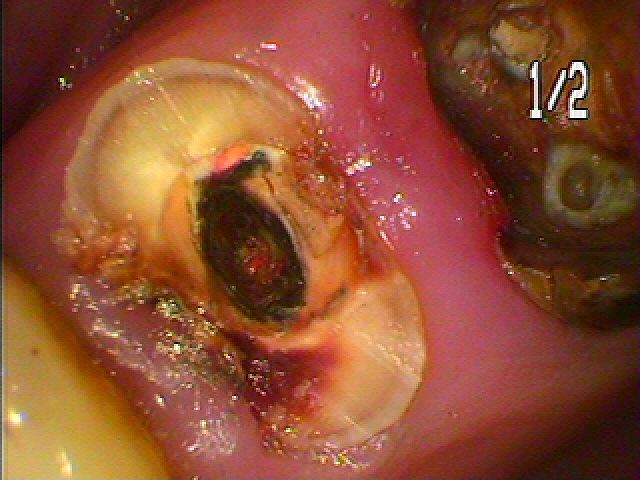

ブログ一覧|広島市安佐南区の歯科医院 ブログ一覧 トップ ブログ一覧 お知らせ スタッフブログ ブログ一覧 お知らせ 2019/04/14 無歯顎のインプラント埋入の補綴構造の難しさ お知らせ 2019/04/14 無歯顎のインプラント埋入には解剖学的に気を付けrなければならない神経、上顎洞などがあるためにどの位置では大丈夫かのステントを使用して判断していきます お知らせ 2019/04/13 上顎の水平埋伏歯 虫歯になっていると歯医者で言われるが、、そこの歯科医院では抜けないといわれ来院 お知らせ 2019/04/13 土台からかぶせが取れた 何とかしてほしい お知らせ 2019/04/12 右上4番 銀歯が見えるので銀歯から白くしたい お知らせ 2019/04/12 セラミック治療 虫歯の治療からの白いセラミック治療 お知らせ 2019/04/11 左下6番の根管治療 前医が根管治療であかなかった根幹になります 難易度があります お知らせ 2019/04/11 難易度の高い根の治療 右下4番2根管 通常は1根管です << 1 2 3 4 5 … 417 418 419 420 421 … 870 871 872 873 874 >> Web診療予約 初めての方へ 選ばれ続ける理由 院内設備について 歯が痛いしみる一般歯科 歯がぐらぐらする歯周病 健康な歯を保ちたい予防歯科 子供の虫歯予防をしたい小児歯科 銀歯をセラミックに審美歯科 白い歯を目指しませんか?ホワイトニング 矯正専門医がいるので安心矯正歯科 抜けた歯を補いたいインプラント・入れ歯 医院案内 スタッフ紹介 メリィハウス歯科クリニックオフィシャルホームページ ラベンダー歯科クリニックオフィシャルホームページ お知らせ・ブログ ホーム 診療科目 一般歯科 歯周病治療 予防治療 小児歯科 審美治療 ホワイトニング 矯正歯科 入れ歯・インプラント マウスピース矯正 初めての方へ 院長・スタッフ 設備紹介 医院案内・アクセス メニューを閉じる